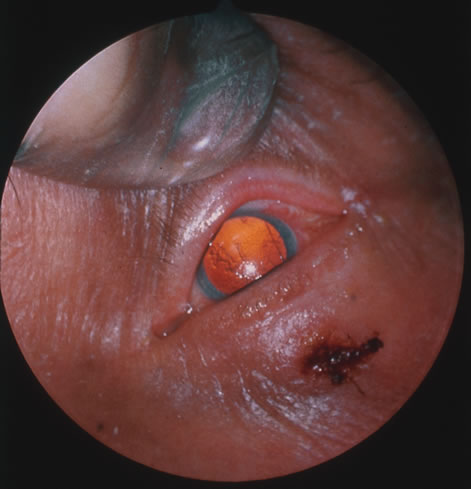

Corneal complications occur in the majority of patients with herpes zoster ophthalmicus. A punctate epithelial keratopathy with pseudodendrite formation is the earliest and most common lesion that occurs. Stromal infiltrates, disciform reactions, and rarely interstitial keratitis are also observed. Scarring and contracture of the lid margin often results in trichiasis, distichiasis, entropion, or ectropion. Corneal sensation is reduced, and neurotrophic ulceration, corneal melting, or perforation may ensue. Extraocular muscle involvement with facial paresis has been observed.11 The acute retinal necrosis (ARN) syndrome is most often caused by the herpes zoster virus, although occasionally it may be a result of herpes simplex infection.12 It is typically described in healthy patients although association with immunosuppressed patients has also been described. Granular, nonhemorrhagic areas of retinal necrosis may be observed in the fundus, often rapidly coalescing with resulting blindness often caused by retinal detachment. There is often an associated vasculitis and vitritis. In immunocompromised patients VZV or HSV retinitis may also take the pattern of progressive outer retinal necrosis (PORN) (Fig. 6). PORN differs from ARN in that the former is multifocal, localized to the outer retina, and is less often associated with vasculitis and vitritis.